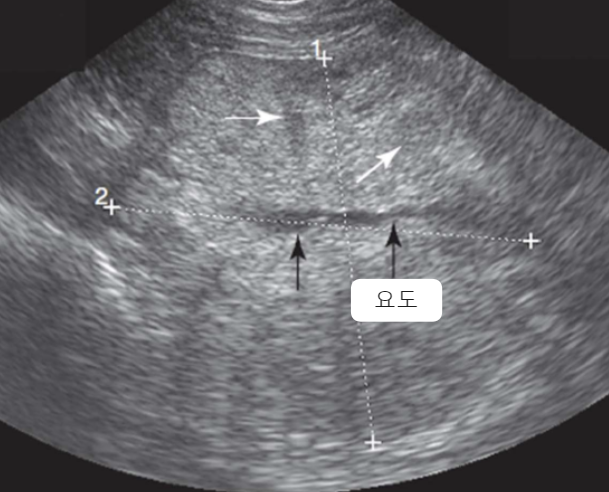

| Ultrasonography (Abd) | _Pyelonephritis |

|---|---|

![]() | - ๋ํ์ ์ผ๋ก ์ผ์์ ์ธ ์ฝฉํฅ ๋น๋ (renal pelvic dilation) - Ureteral dilation (์๊ด ํ์ฅ) - Blunting of the renal papilla (์ฝฉํฅ์ ๋์ ๋ํ) - Echogenic debris (๋ด๋ถ์ ๊ณ ์์ฝ์ฑ ์ํด) * ์ ์ฐ์ ์ผ์ธ๋ฐ ์ฝฉํฅ์ด ์ถ์๋์ด ์์ผ๋ฉด, CKD๋ ๋ง์ฑ ์ ์ฐ์ ์ผ์ ์์ฌํด๋ณด์. + Bacterial culture : pyelocentesis(์ ์ฐ์ฒ์)๋ ์ค์ง์ ๊ฑด๋๋ฆด ์ ์์ผ๋, ๋ฐฉ๊ด sampling๋ถํฐ ์๋ |